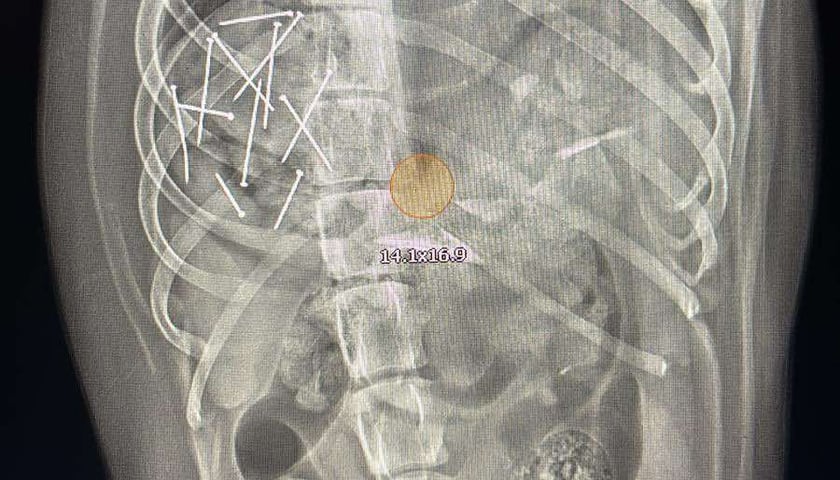

Powiększ obraz: <p>Zdjęcie rentgenowskie Ory. Po lewej stronie widać 12 gwoździ w psim żołądku</p> fot. Stowarzyszenie 4 Łapy Wrocławia

Zdjęcie rentgenowskie Ory. Po lewej stronie widać 12 gwoździ w psim żołądku

-  Gdy znalazłem na poboczu jeszcze kilka takich kawałków, zabrałem psa na ostry dyżur. Po prześwietleniu okazało się, że ma w żołądku 12 gwoździ - opowiada Krzysztof Lepski, który adoptował Orę 2 lata temu.

Gdy lekarz dyżurny zobaczył, co tkwi w psim żołądku, natychmiast wezwał chirurga. Na szczęście operacja nie była konieczna, ale zabieg wyciągania gwoździ trwał kilka godzin.

– Udało mi się zlokalizować gwoździe przy pomocy endoskopu i wyjąć je, jeden po drugim, przez jamę ustną psa– mówi Alicja Wajda, chirurg z Kliniki Weterynaryjnej dr n. wet. Dariusz Niedzielski Wrocław. – Ich część wbiła się w błonę śluzową żołądka, jednak na szczęście nie doszło do jego perforacji. W tej chwili życiu zwierzęcia już nic nie zagraża.